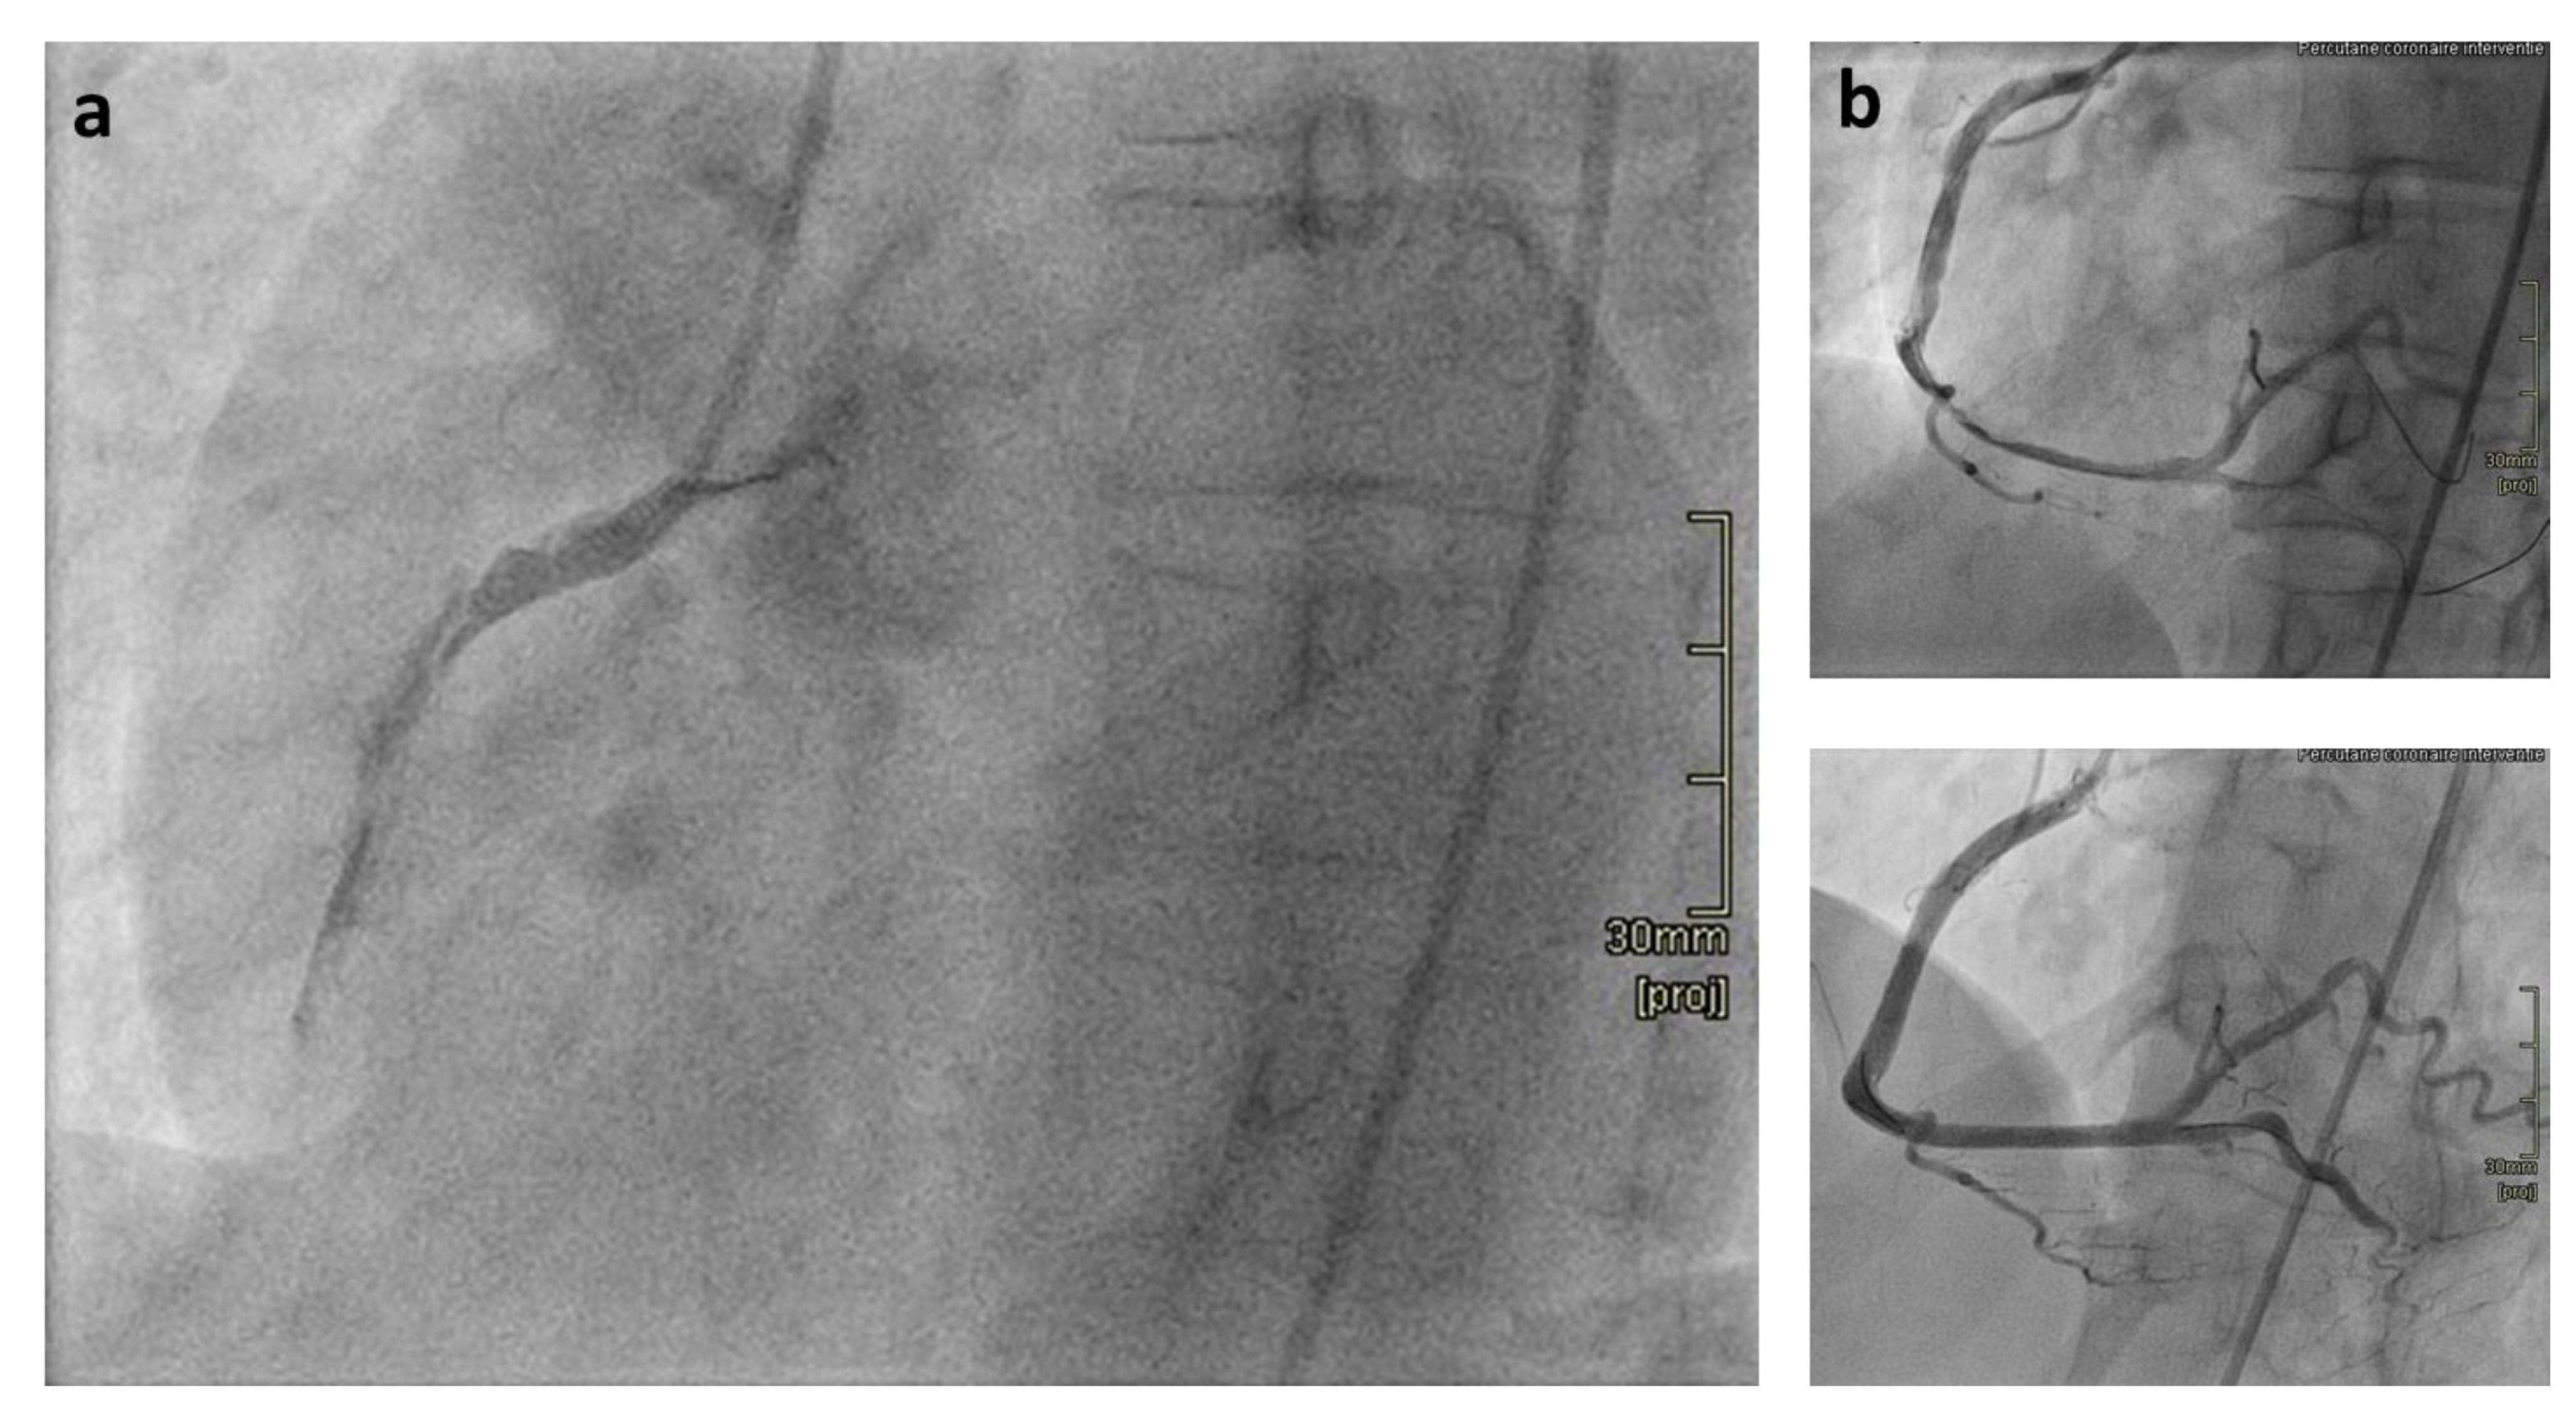

Spontaneous Coronary Artery Dissection as Presenting Feature of Vascular Ehlers-Danlos Syndrome

:1. Introduction

2. Discussion